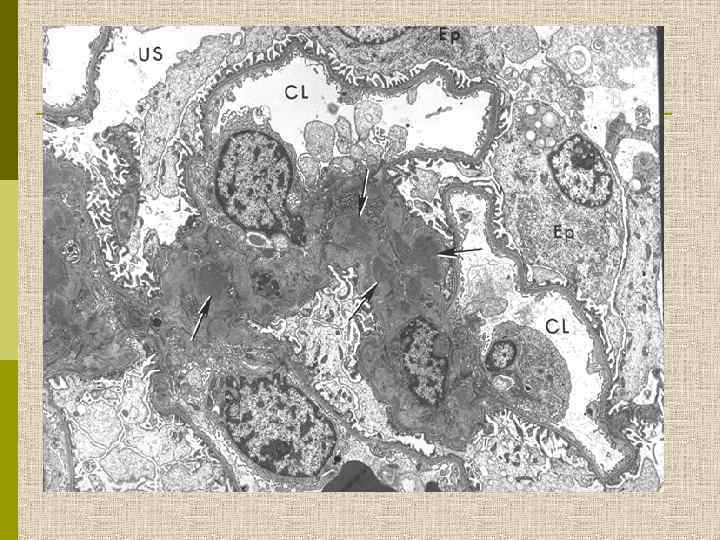

Мезангиопролиферативный гломерулонефрит (электронноплотные депозиты в мезангии)

Морфология Ig. А-нефропатии q Определяющий симптом – диффузные отложения Ig. A в мезангии, коррелирующие с электронноплотными депозитами в мезангии при электронной микроскопии q Могут наблюдаться депозиты С 3, Ig. G, реже Ig. M, а также Ig. A в капиллярной стенке q При световой микроскопии – от минимальных изменений до сегментарной или диффузной мезангиальной гиперцеллюлярности, с развитием фокального сегментарного склероза, атрофии канальцев и интерстициального фиброза q При электронной микроскопии – высокая частота фокального истончения ГБМ